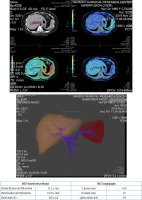

As demonstrated in Figures 5 and 6, the sample indicators of liver perfusion are shown in both health and LC states. It is also important to note that MSCT examinations allow for the identification of the particular features of the portal system angioarchitecture. This is important in the planning of surgical options, including palliative surgeries such as portosystemic shunting or disconnecting interventions, as well as definitive treatment, i.e. liver transplantation. The visualisation of vasculature facilitates the identification of distinctive features in the architecture of the portal and arterial systems.